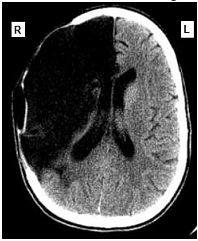

Uma mulher de sessenta e dois anos de idade foi levada pelo acompanhante ao atendimento médico de um hospital, às 7 horas e 30 minutos da manhã. O acompanhante relatou que a paciente tinha sofrido uma queda no banheiro de sua residência enquanto tomava banho, às 6 horas da manhã, e que ele a havia encontrado minutos depois. A paciente não conseguia mover o braço e a perna esquerdos, falava de forma lenta e arrastada, mas com sentido lógico. No exame clínico, foram observadas pressão arterial de 160 mmHg × 95 mmHg, ausculta cardíaca com ritmo cardíaco irregularmente irregular e frequência cardíaca de 98 bpm, sem sopros. A paciente estava com lentidão para responder a questionamentos, apresentava pupilas isocóricas e fotorreagentes, diminuição da sensibilidade dolorosa no lado esquerdo da face, paralisia facial central, hemiparesia flácida do hemicorpo esquerdo (mais acentuada nos membros superiores), reflexos profundos mais acentuados à esquerda e sinal de Babinski à esquerda. No eletrocardiograma realizado foram detectados ritmo de fibrilação atrial, com frequência ventricular média de 100 spm, SÂQRS = -30º, sinais de sobrecarga ventricular esquerda e alterações difusas e secundárias da repolarização ventricular. A tomografia computadorizada do crânio, sem contraste, realizada na paciente, apresentou o resultado mostrado a seguir.

Internet:<www.emedicinehealth.com> (com modificações).